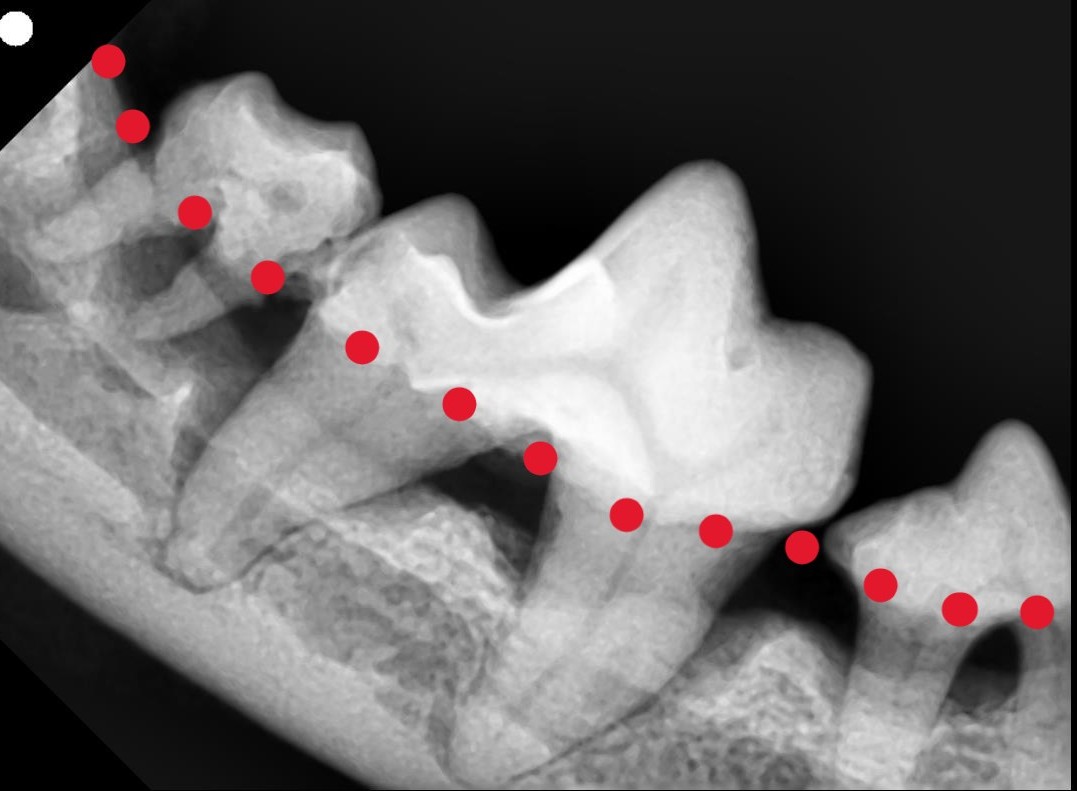

レントゲンで発見された埋没歯~折れた歯の根が残っていました~

🦷犬の埋没歯(歯の破折後に歯が埋まってしまったケース)~見えない歯の中で起きているトラブル~ 写真は、歯が折れたあとに残った歯根が歯ぐきの中に埋まってしまった状態を示しています。 このような「埋没歯(まいぼつし)」は、外から見ただけではわかりにくく、...

写真で見る歯科レントゲン 上のレントゲン写真は、犬の奥歯を撮影したものです。 1枚目(異常):赤い点線より下の部分は本来骨がしっかりとあるはずですが、歯周病によって骨が溶け、歯が支えられなくなっています。 2枚目(正常):歯の根まで骨がしっかり残っており、健康な状態です。...